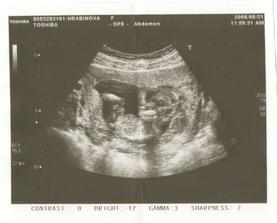

♥ 10.7.08 - 20+5tt / velký UZ v Motole. Miminko je zdravé. Má asi 380g a něco přes 20 cm. Je přesně akorát na svůj věk 🙂 TP 23.11.08